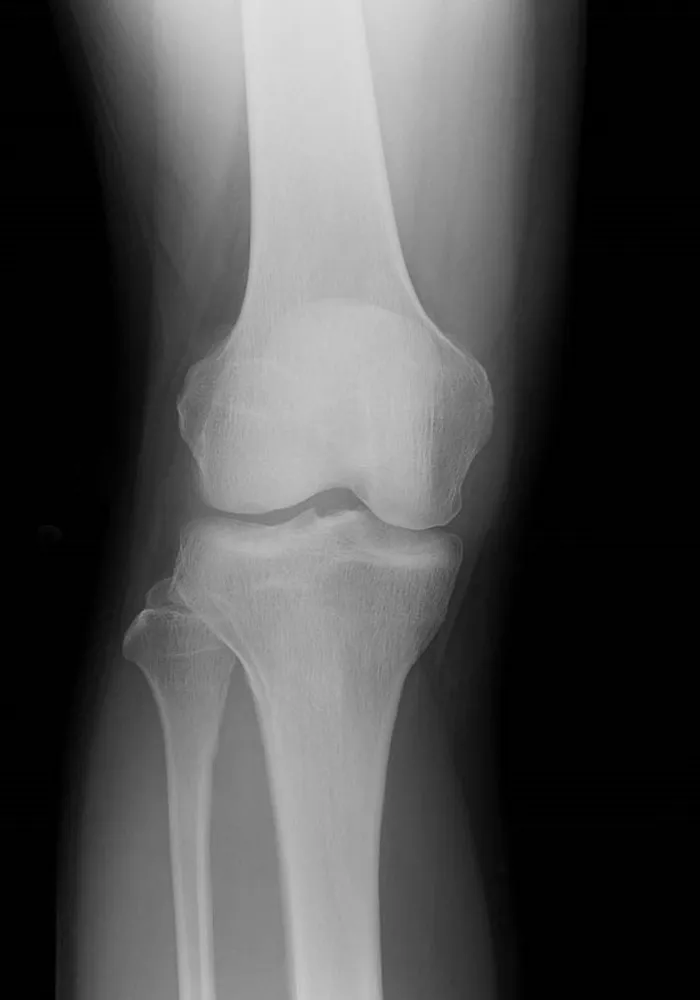

一般撮影

一般撮影は診断目的とする部分にX線を照射して撮影を行う検査です。X線は体内を通過する際に骨や筋肉、内臓などの組織により吸収される量が変化するので、透過したX線量の差を画像化したものがレントゲン写真となります。

当院の一般撮影室は 2室 あり、いずれも フラットパネルディテクタ(FPD)対応 の最新機器を導入しています。FPDを用いることで、従来よりも少ないX線量で効率的に撮影でき、より高画質な画像を得ることが可能です。これにより、患者様の被ばく線量をできる限り低減しつつ、迅速で正確な診断に役立てています。